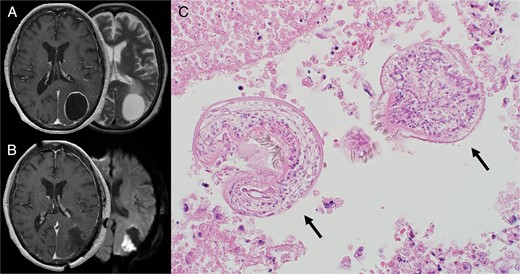

On admission, she presented nausea with a neurological examination revealing right homonymous hemianopia, anarithmia, agraphia, and finger agnosia without lateral agnosia (incomplete Gerstmann syndrome). Gadolinium-enhanced T1-weighted magnetic resonance imaging (MRI) of the brain revealed a single cystic lesion in the left parietal lobe with a diameter of 44 mm surrounded by a contrast-enhanced smooth rim with a small daughter cyst (Fig. 2A). A mild edema was observed mainly ventral to the cyst (Fig. 2A). The patient was suspected to be suffering from CAHC based on the past medical history of HAHC.

(A) Preoperative MRI. Axial contrast-enhanced T1-weighted (left) and T2-weighted MRI (right) demonstrated a ring-enhancing cystic lesion in the left parietal lobe with edema extending ventrally. (B) Postoperative MRI. Axial contrast-enhanced T1-weighted image (left) showed complete cyst resection. Diffusion-weighted image (right) showed cerebral infarction adjacent to the cyst wall caused by vascular injury during the operation. (C) HE staining of the cyst showed two protoscoleces (black arrows). Alt text: Preoperative MRI images of brain Echinococcosis at the top left and postoperative MRI images showing complete cyst resection at the bottom left. A microscopic image on the right is a Hematoxylin and eosin (H&E) stained specimen showing two protoscoleces.

A surgical resection of the cyst was performed to deal with the cyst’s intracranial mass effect. The cyst was found to be covered with hard, fibrous tissue. Despite extreme caution not to rupture the cyst, the strong adhesion with the arachnoid membrane of the cyst wall’s posterior region tore, and some internal fluid disseminated to the surgical field. The disseminated fluid was turbid and immediately aspirated to prevent further dissemination, followed by replacing the cyst content with 95% alcohol, referring to the PAIR technique. The cyst wall was removed entirely after aspirating the injected alcohol (Fig. 2B). Histological examination confirmed the presence of CAHC (Fig. 2C).